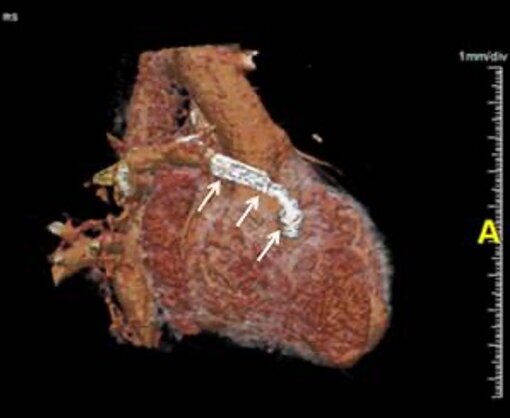

Sagittale Rekonstruktion mit operativ angelegtem Bypass (Pfeile) zwischen dem rechten Ventrikel und der Pulmonalarterie. Strahlenbelastung von 0,9 mSv.